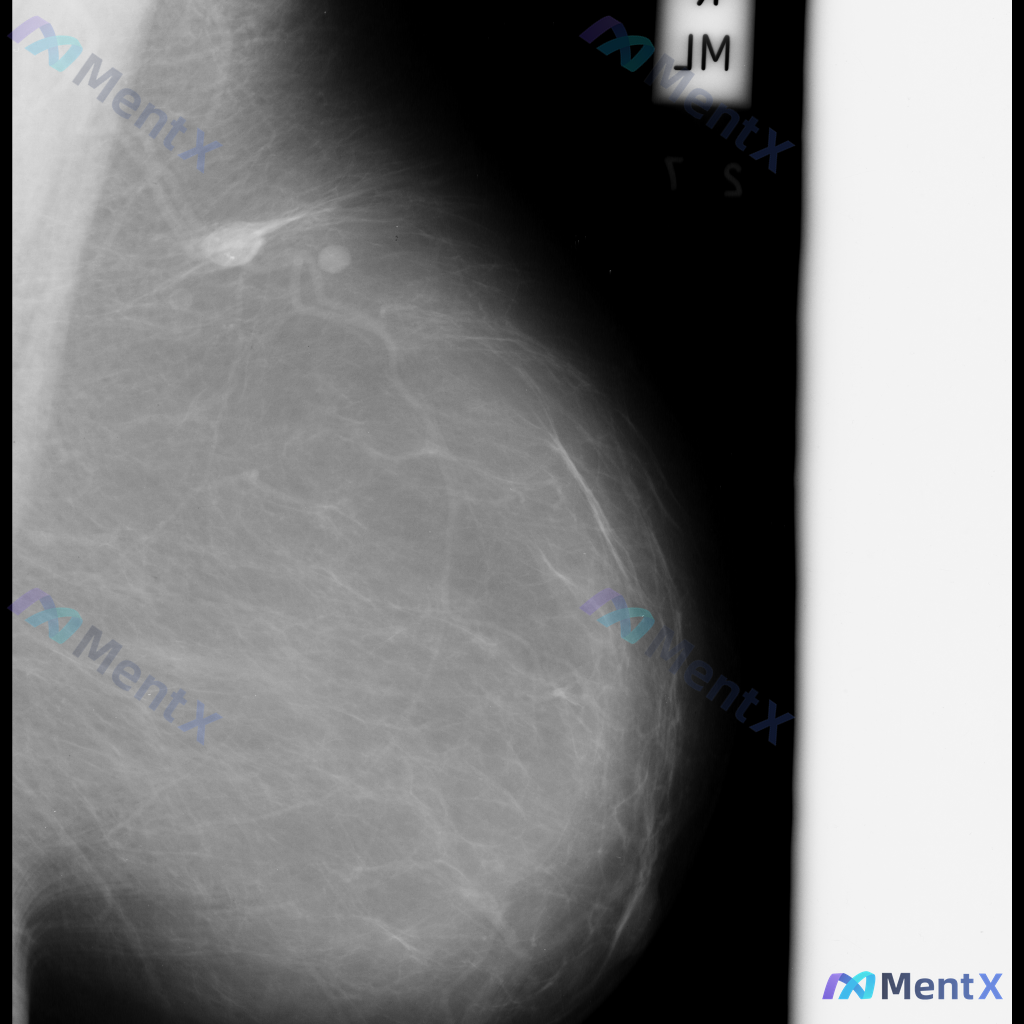

整理到一张乳腺钼靶影像资料,主要表现如下:

- 乳腺内可见一个较大的肿块,形态不规则,边界部分模糊、呈毛刺状,密度较高,同时伴有明显的结构扭曲;

- 另外还存在一枚较小的圆形、边界相对清晰的高密度结节。